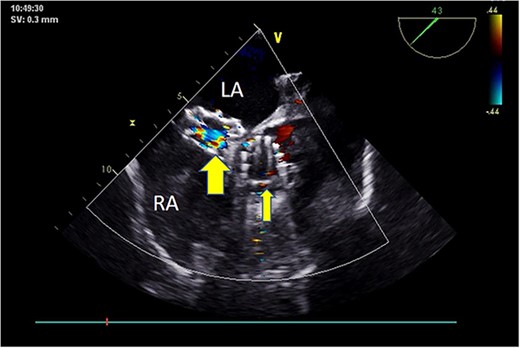

Intraoperatively, after self-expanding the aortic valve, TEE monitoring confirmed excellent cardiac function, disappearance of aortic valve regurgitation, secure anchoring of the aortic valve prosthesis, and no obstruction to the mitral valve leaflets or coronary ostia. The aortic valve velocity and pressure gradient upstream of the valve decreased compared to preoperative values, with a maximum velocity of 166 cm/s and a pressure gradient of 11 mmHg (Fig. 3). However, a periprosthetic leak with a residual width of ~4.5 mm was observed at the self-expanding valve’s interface with the native annulus (Fig. 4). Based on preoperative data, the decision was made to re-expand and reshape the prosthesis. Postdilation, TEE monitoring showed a reduction in the periprosthetic leak to 1.5 mm (Fig. 5), a significant improvement compared to predilation. Following satisfactory self-expansion results, the planned percutaneous ASD closure procedure was performed under ultrasound guidance. The closure device was securely positioned in the atrial septum, and TEE examination showed no deformation or impingement of the self-expanding valve (Fig. 6). Atrial shunting was eliminated, and the outcome exceeded expectations.

Postoperative TEE: Short-axis TEE displays circular echoes in the self-expanding valve (thick arrow) with good morphology and position. The sealing umbrella (thin arrow) maintains a proper shape and fixed position, eliminating left-to-right atrial-level shunt.